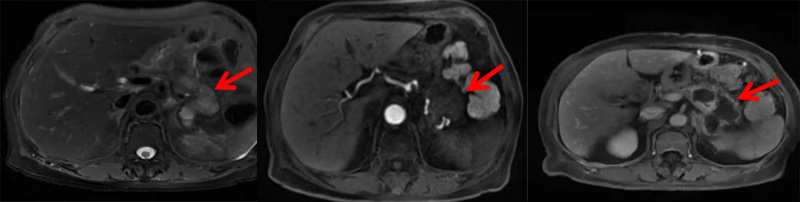

术后第3天,王奶奶顺利出院。术后一月复查中上腹增强MRI显示:消融部位无明显肿瘤活性,未见肿瘤复发灶。

▲ 术后1月复查核磁共振,肿瘤完全灭活